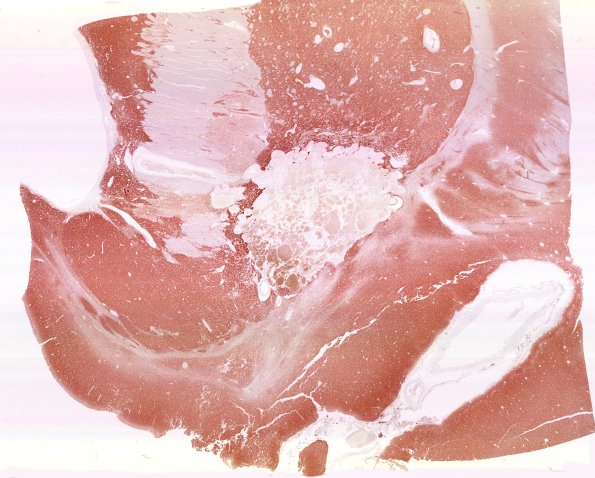

31G1 Cavernoma (Case 31) SYN WM

This whole mount shows that brain parenchyma is excluded from the cavernous angioma. (SYN IHC)